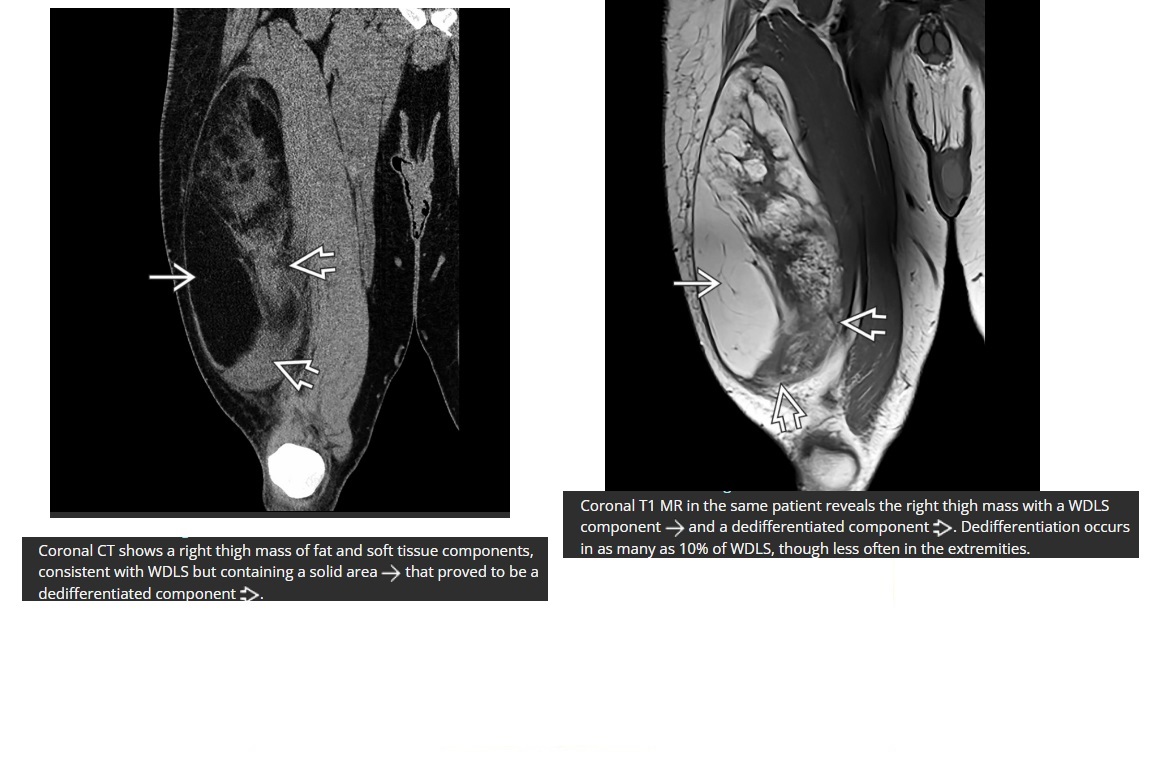

well differentiated liposarcoma

*>75% fat content

*thickened septa

*small soft tissue nodularity

commonly located in the retroperitoneum

if develops a clear cut separate nodular/soft tissue dominant focus > 1 cm = de-differentiated

if < 20

= Myxoid liposarcoma often shows a classic myxoid background (T2/STIR-bright) with some nodular soft tissue

and adipose tissue components. Don’t confuse for cyst!!!